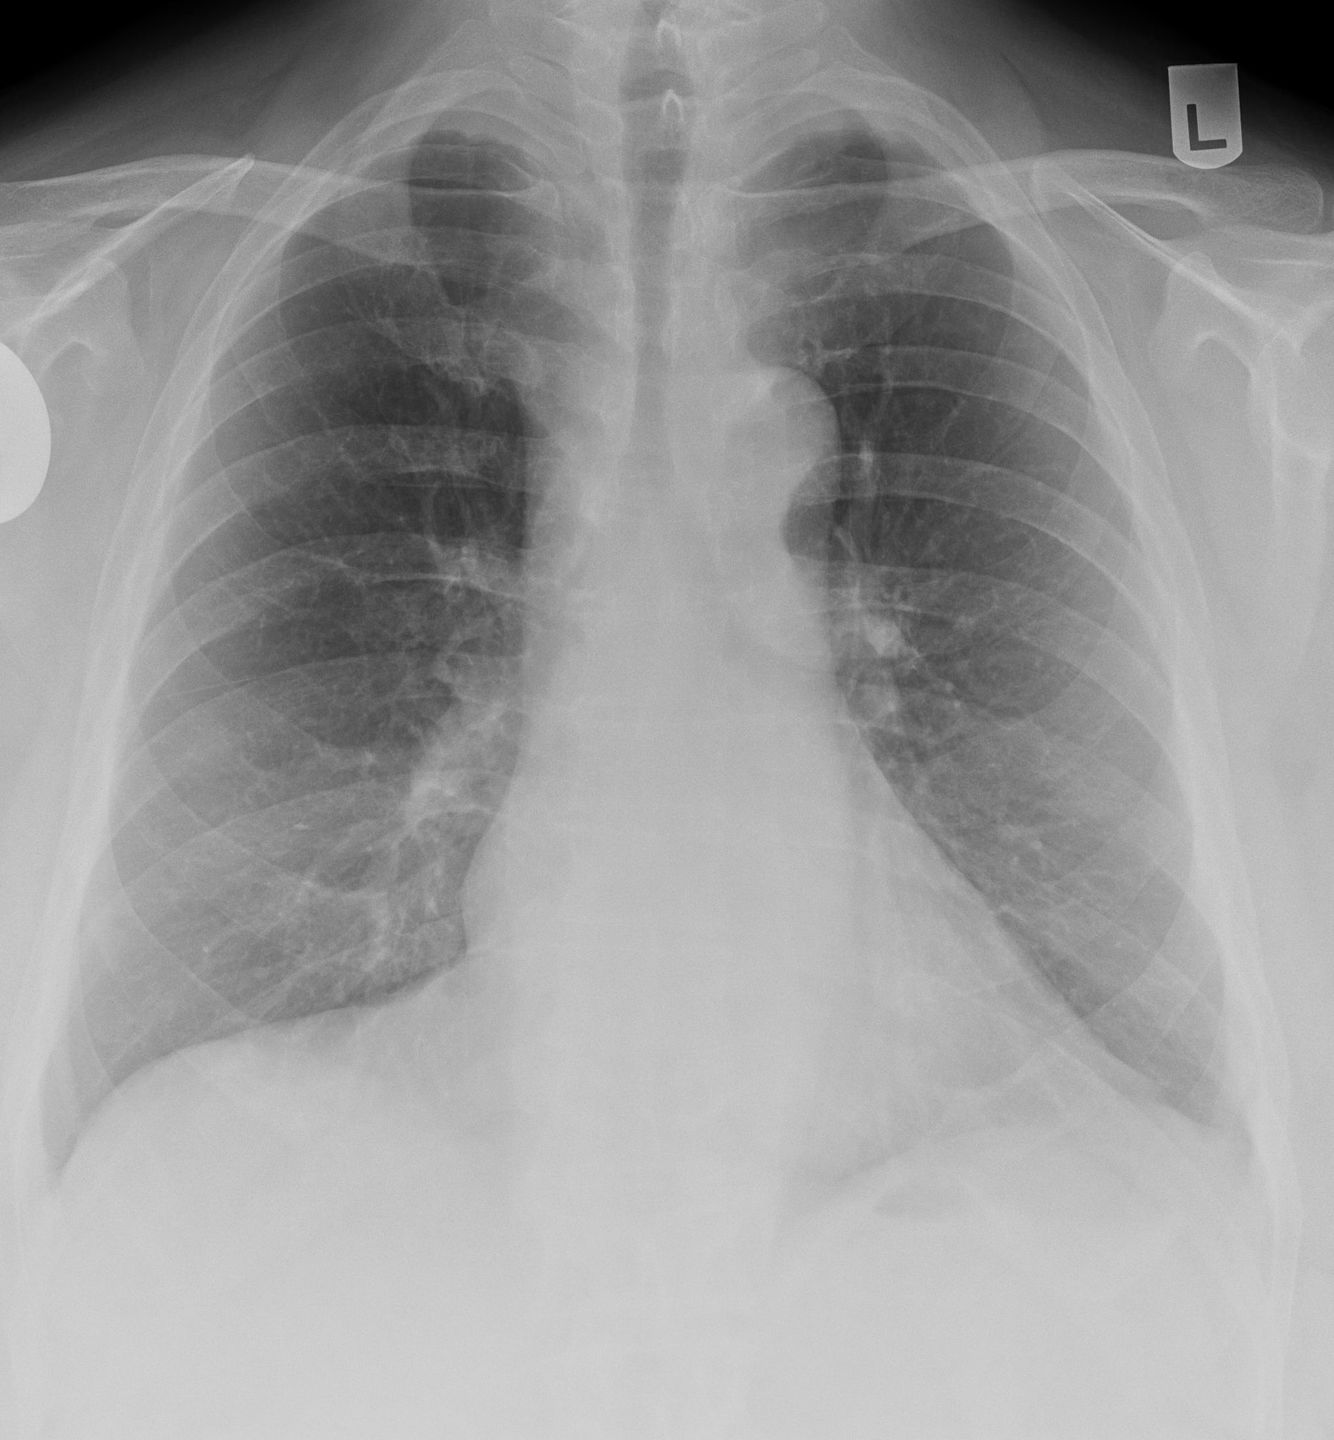

Plain radiograph

There are no pathognomonic radiological features specific for asbestosis 1. Chest radiograph may show irregular opacities with a fine reticular pattern. Additional evidence of asbestos exposure such as calcified or noncalcified pleural plaques may be evident.